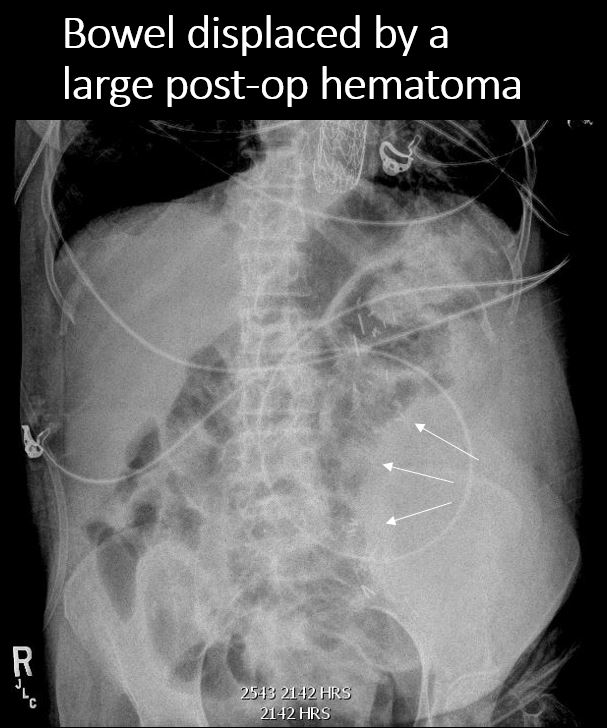

49 year old male with abdominal pain. Previous history of GSW.Exam